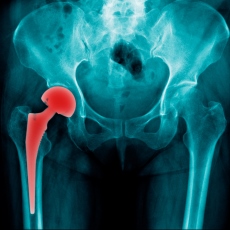

Hip replacement is surgery for people with severe hip damage. The most common cause of damage is osteoarthritis. Osteoarthritis causes pain, swelling, and reduced motion in your joints. It can interfere with your daily activities. If other treatments such as physical therapy, pain medicines, and exercise haven't helped, hip replacement surgery might be an option for you.

During a hip replacement operation, the surgeon removes damaged cartilage and bone from your hip joint and replaces them with new, man-made parts.

The most common problem after surgery is hip dislocation. Because a man-made hip is smaller than the original joint, the ball can come out of its socket. The surgery can also cause blood clots and infections. With a hip replacement, you might need to avoid certain activities, such as jogging and high-impact sports.